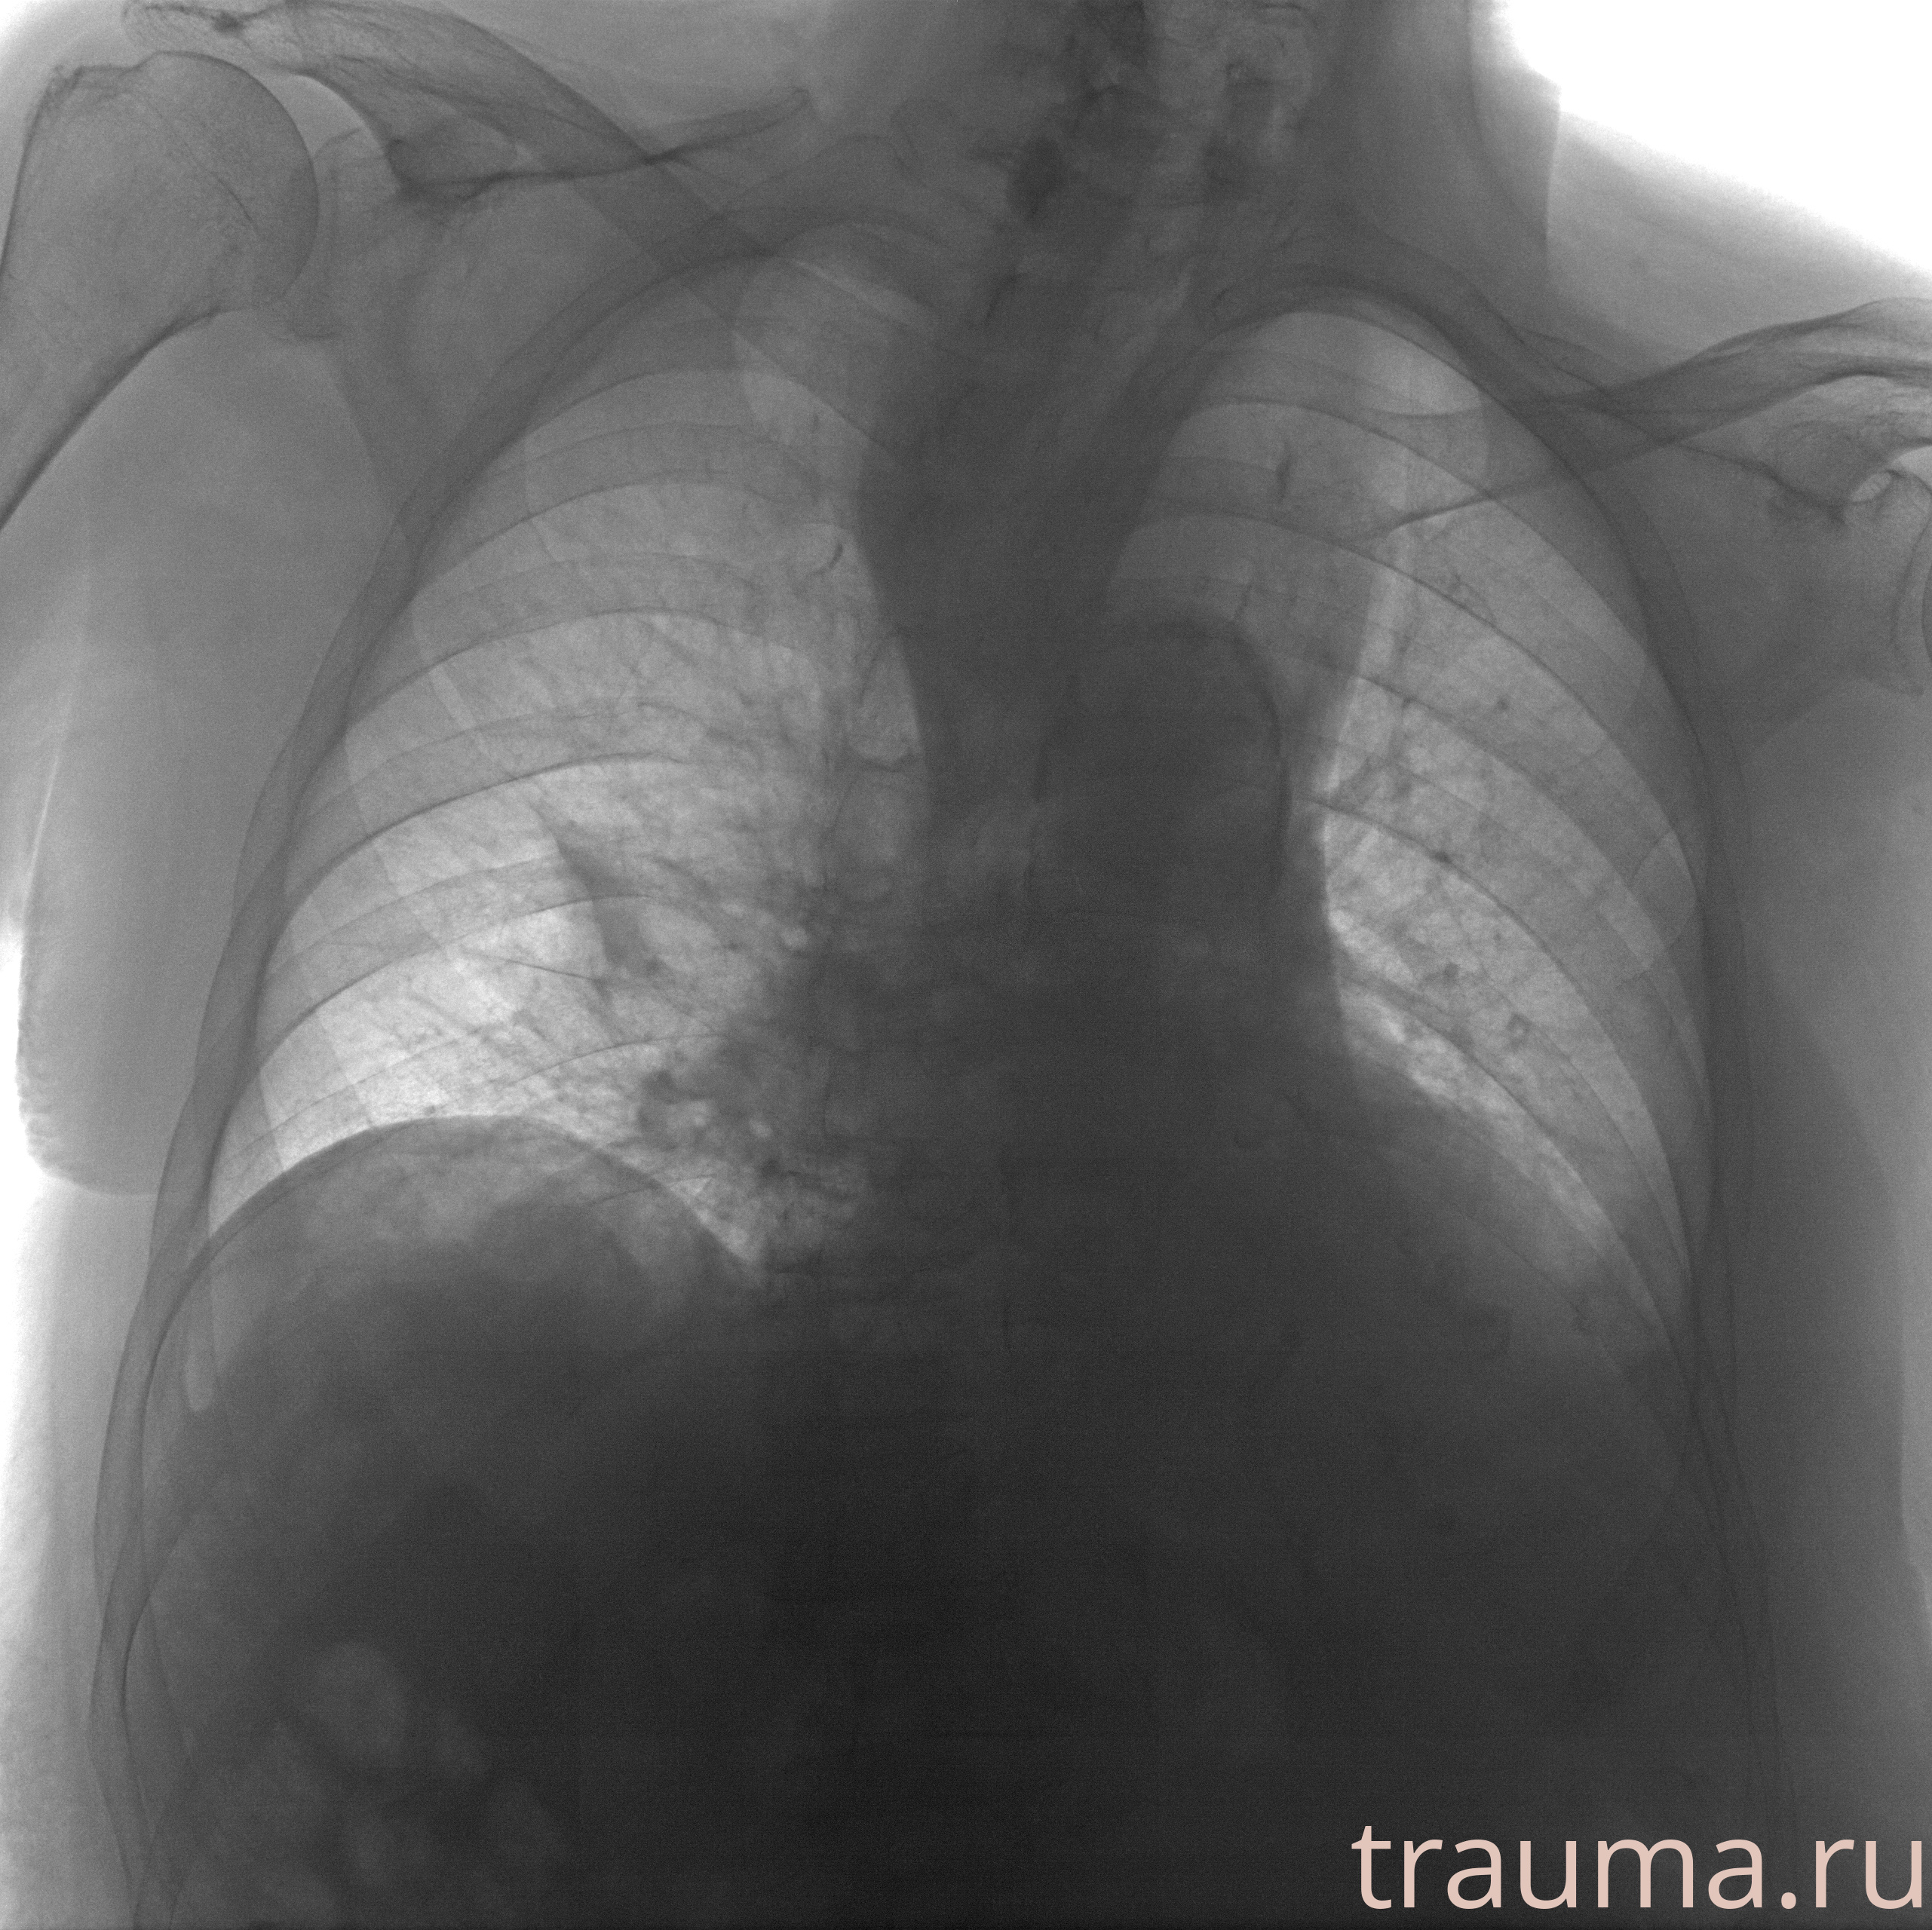

Рентгенограммы

Рентген на дому: по вашему адресу приезжает врач-рентгенолог, травматолог-ортопед с мобильным рентгеновским аппаратом, проводит диагностику травмы или заболевания, делает необходимые рентгенограммы, дает рекомендации по дальнейшему лечению. Получить качественные снимки в домашних условиях возможно благодаря уникальной методике, разработанной МосРентген Центром для института  Склифосовского

при переломе шейки бедра и пневмонии от компании МосРентген Центр - партнера Института имени Склифосовского